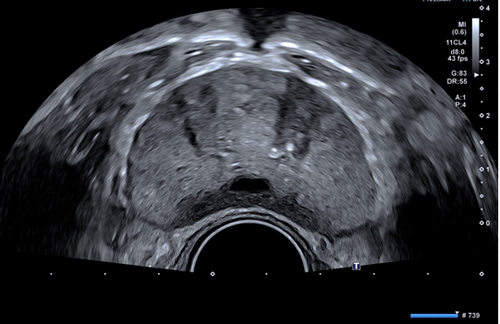

自临床使用以来,检查医生都反应二维图像很清晰,特别是一些新增功能,更受欢迎。1.彩超血流技术除常规CDFI、高级动态血流技术外,还具备超微细血流技术,能检测极低速血流(流速0.1-0.4cm/s),而微细低速血流广泛存在于各类疾病病灶的滋养血流、新生血流,能快速、便捷的帮助超声医生对疾病的准确诊断和鉴别诊断。2.声衰减成像功能,可对肝脏组织的衰减系数进行测量及可视化显示,可以对脂肪肝作出量化诊断,是诊断脂肪肝的有效定量工具。早期发现和量化评估肝脂肪变性,利于及时处理,防止病程进展。3.双平面探头(凸阵+线阵),为前列腺穿刺、肛周脓肿、阴道尿道、盆底功能障碍等疾病的诊断治疗提供不可替代的优势。凸、线双平面探头在前列腺、肛周穿刺活检中,实时快捷观察冠状面、矢状面,确定穿刺针路径、位置,提高穿刺活检成功率。4.浅表微小钙化增强显示技术,显著提升0.1-0.2mm微钙化点的检测识别能力。可以与原始图像实时双幅对比显示,可应用在乳腺、甲状腺等腺体组织恶性肿瘤的早期筛查。5.术中探头,配置穿刺引导架、能提高肝、肾等腹腔脏器的穿刺准确率。